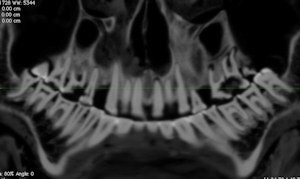

Curved planar reformatted CT image. Note the carious lesions on the left first and second molars. Image courtesy of Andrew D. Wade, PhD.','dvPres', 'clsTopBtn', 'true' );" >

Curved planar reformatted CT image. Note the carious lesions on the left first and second molars. Image courtesy of Andrew D. Wade, PhD.

Overall, the dental condition of the mummy is poor, the researchers reported. The maxillary and mandibular teeth show occlusal attrition and abrasion, while the maxillary teeth also have numerous periapical abscesses and large interproximal carious lesions.

"Abscesses were found at the apices of the maxillary right first molar and second incisor and of the left first incisor and molars," they wrote. "The abscesses of the left maxillary molars communicate with the maxillary sinus and inferior meatus. Interproximal caries are noted in the maxillary right second premolar."

The researchers also identified the mass previously found by Dr. Langsjoen in the carious lesions of the left first and second molars, and described it as a low-density, homogeneous ball of material, such as linen. It measures 7.7 x 7.1 x 3.7 mm, larger than the lesion's opening of 5.5 x 6.8 mm, but it remains loose within the cavity, they noted.